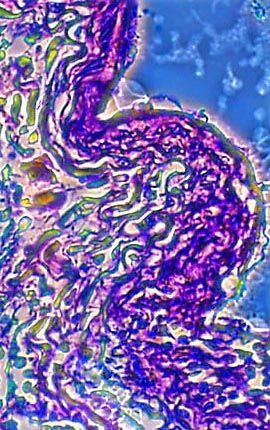

A stained thin section of human lung tissue exhibiting damage from bronchiogenic carcinoma is illustrated above. As evidenced by the micrograph, combining phase contrast microscopy with classical histological staining techniques in pathological research often yields enhancement of cellular features.